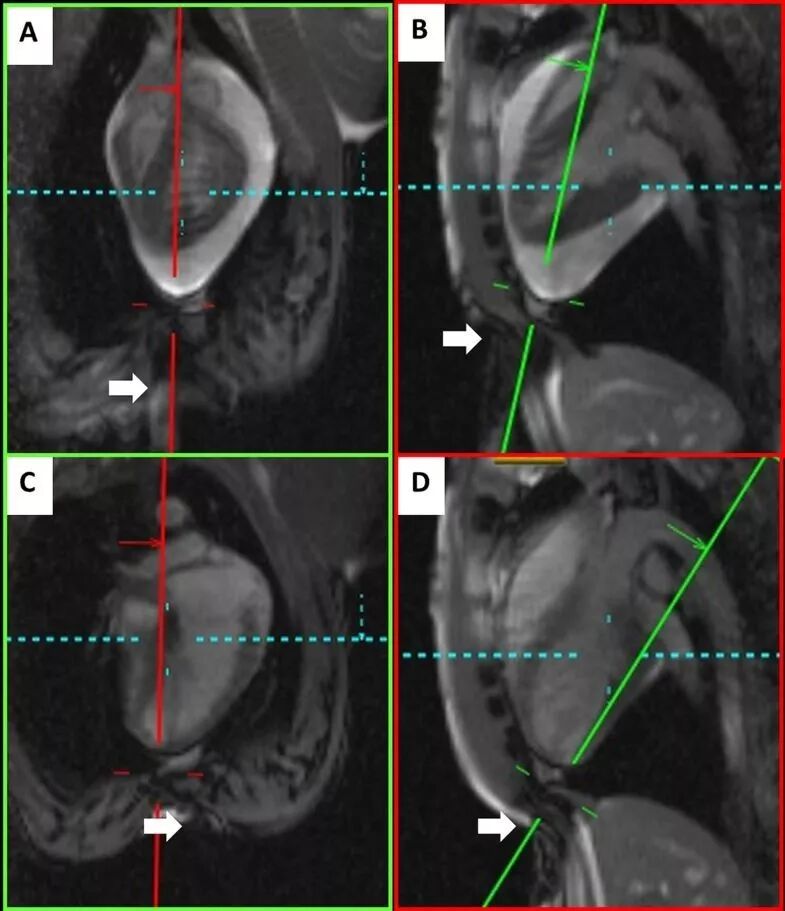

[1] Halabi M, Faranesh AZ, Schenke WH, et al. Real-time cardiovascular agnetic resonance subxiphoid pericardial access and pericardiocentesis using off-the-shelf devices in swine. J Cardiovasc Magn Reson. 2013, 20(15): 61.

[2] Fukuzawa K, Mori S, Kiuchi K, Nishii T, Hirata KI. Percutaneous Pericardiocentesis for Epicardial Ventricular Tachycardia Ablation With the Anterior Approach Not Passing Through the Abdominal Cavity. JACC Clin Electrophysiol. 2017, 3(5): 526-527.